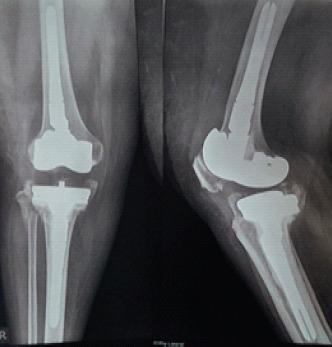

A 52-year-old female with RA sustained a right knee PPF following a trivial fall. Clinical and radiographic evaluation classified the fracture based on prosthetic stability and bone quality:• Type II fracture with a loose prosthesis requiring revision surgery.She underwent staged revision TKA including:1.Definitive surgery with revision TKA and bone grafting in figure.2.Postoperative rehabilitation to restore function figure.

1. 确定性手术,进行翻修TKA并如图所示植骨。

2. 术后康复以恢复功能,如图所示。